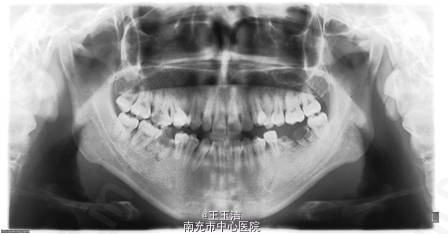

主诉:“地包天”要求矫治。 女,22岁,地包天,生长发育停滞期,全身病史:无特殊

长面型,下面高偏大;C6、D67残冠 ;磨牙关系Ⅲ类,前牙及前磨牙反合,无咬合接触 ;spee曲线平;上颌拥挤量8mm,下颌拥挤量6mm.;上前牙唇倾,下前牙舌倾。前牙及全牙Bolton比正常。

诊断:安氏Ⅲ类,骨性Ⅲ类,垂直生长型,反合伴前牙开合,牙列拥挤 处理:全口直丝弓矫治技术+正颌外科手术(SSRO) 拔除A4B4 C6D67,去代偿 前移上后牙关闭剩余间隙,维持下颌拔牙间隙,后期修复治疗 结束固定正畸治疗后,上颌用透明保持器保持,下颌全牙弓夹板型可摘义齿保持。